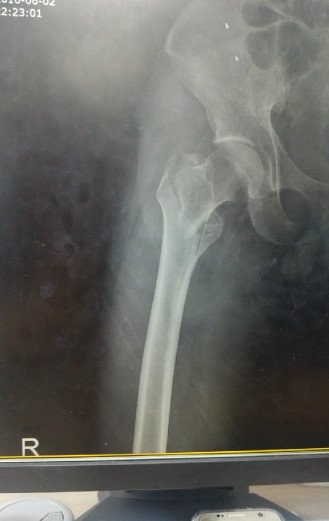

철심을 이렇게 박았습니다.

저는 실려가서 허벅지 뼈가 부러지는 대퇴골 골절상을 비롯해 가슴 팔 다리 부분이

찢어지는 상해를 입었습니다. 다시 큰 대학병원으로 옮겨서 대퇴골 골절 수술을 했습니다.

철심 길게 하나 양쪽으로 2개 핀1개꽂고 대수술을 했습니다. 수술걸린시간은 5시간정도고요

이수술은 거의 노인분들만 하고 젊은층은 10%도 안되는 수술이라고하네요....

목발은 3개월정도 짚어야되고 허벅지에 철심은 1년뒤에 다시 빼는 수술을 해야한다고 ....